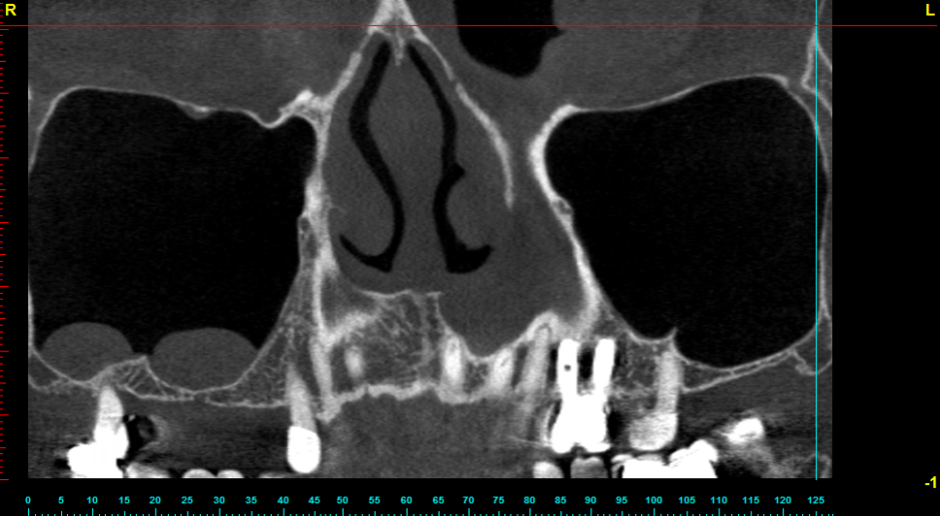

In this site I’ll be posting random dental snip its. In this case, we used this timeline for a recent sinus lift. I’ve never done one just participating with the faculty on this one. This is the timeline we went in with. It actually took much longer. Leave any comments below about what you may do differently or any thoughts about the procedure.